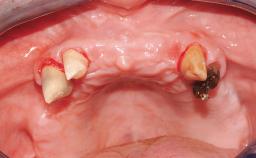

Immediate Loading of Eight Implants in the Maxilla and Six Implants in the Mandible and Final Restoration with Three-Unit and Four-Unit FDPs

Extensive scientific evidence has confirmed that immediately loaded implants with fixed full-arch provisional restorations can osseointegrate with success rates similar to conventionally or delayed loaded implants. A number of immediate-provisionalization techniques for edentulous jaws have been described. Some protocols differ when it comes to prefabricated provisional templates versus complete denture conversion; intrasurgical impressions versus direct relining; and cemented versus screw-retained provisional restorations. In this context, complete-denture conversion has been proposed for either intrasurgical impressions or direct relining. Another possibility is the utilization of a prefabricated provisional to be adapted either in the mouth (by direct relining) or in the laboratory (on a working model obtained from an intrasurgical impression).

Case Type Edentulous Maxilla

Defining Characteristics Fully edentulous upper jaw to be rehabilitated with four or more implants

Bone Volume Horizontally and vertically sufficient

Soft Tissue Contour and Volume Slightly compromised